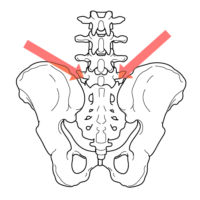

ただし、腰椎などのサブラクセーションによる、神経コントロールができずに腸が動かなくなっている便秘には効果はないですけれど。そんなときには、当院にご相談くださいね。